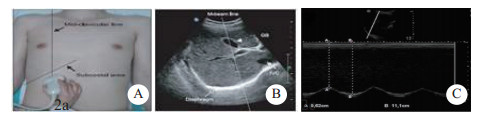

患者取仰卧位,暴露胸部及上腹部,在呼吸平稳后,利用超声凸阵探头(Sonosite M-Turbo 2~5 MHz),在双侧锁骨中线肋弓下,取样线尽可能与膈肌影像垂直,夹角最大不超过20°。应用M超模式记录膈肌与体表探头的距离。SBT 30 min后,测吸气相与呼气相的膈肌移动距离之差,分别测双侧膈肌移动度的数值,取平均值,称为膈肌移动度(即为DD),并记录,见图 1~2。

| A:膈肌检查部位于双侧锁骨中线肋弓下;B:获取的右侧膈肌超声图片(A、B图片来源:Ferrari G, De Filippi G, Elia F, Apra F, et al.Diaphragm ultrasound as a new index of discontinuation frommechanical ventilation. Crit Ultrasound J.2014 Jun 7;6(1):8)。C:表示M超模式下膈肌在吸气相与呼气相的运动幅度,虚线A代表呼气相膈肌距离探头的距离,虚线B代表吸气相膈肌距离探头的距离,线B的长度减去线A的即为膈肌移动度,即DD 图 2 膈肌超声检查及数据收集方法 |